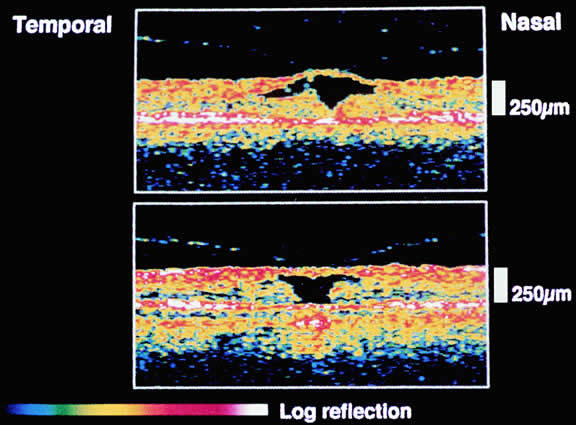

The mechanical relationship between the vitreous and the retina is mediated by the posterior vitreous cortex, which is also called the posterior hyaloid. The posterior vitreous cortex consists of relatively densely packed type II collagen fibrils arranged tangentially to the retina. The retinal basal lamina is the basement membrane of the Müller's cells that comprise the internal limiting membrane (ILM) of the retina.6,7 Ultrastructurally, the ILM consists of three layers.8 Adjacent to the end feet of the Müller's cells is the lamina rara interna. The lamina rara externa is contiguous with the vitreous cortex. In between these layers is the lamina densa. Collagen fibers of cortical vitreous are tangential to the lamina rara externa. The ILM is composed of primarily type IV collagen but also contains fibronectin, laminin, and type I collagen.9 The morphology of the ILM varies topographically in the retina. The ILM, and in particular the lamina densa, is thin in the retinal periphery and becomes increasingly thicker and irregular in the posterior retina.6,8

The ILM thickens from 50 nm at the vitreous base to 300 nm at the equator to 1900 nm posteriorly. In the foveal region the ILM thins to 10 to 20 nm.10

The nature of the adhesion between the vitreous cortex and the ILM is enigmatic. This adhesion is strongest at the optic nerve, the macula, the vitreous base, and retinal vessels. Foos6 demonstrated attachment plaques between Müller's cell cytoplasm and the ILM in the basal and equatorial retina (Fig. 2). Vitreous traction mediated by vitreous fibrils may contribute to these adhesions. These attachment plaques are not present posterior to the equator except where the ILM is thinned in the fovea. This anatomic variation in the fovea region may play a role in the pathogenesis of some of the vitreomacular disorders.

The ILM also thins over major blood vessels. Vitreous strands extend through pores in the ILM to surround the vessels11 and have been termed vitreoretinovascular bands.12 These bands may explain the strong adhesion between the vitreous and retinal vessels.